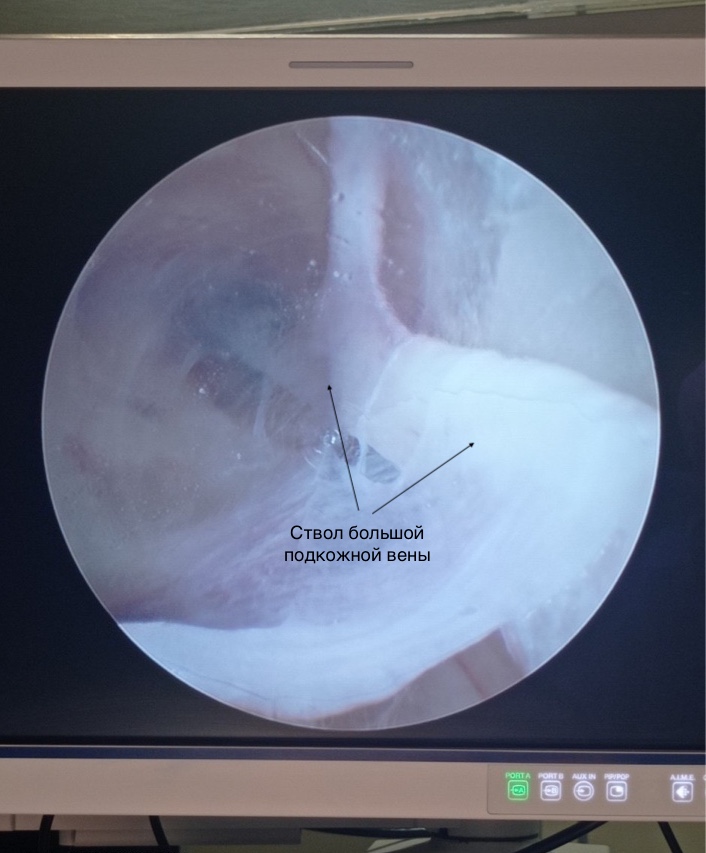

В отличие от стандартного открытого способа выделения большой подкожной вены, при котором требуется почти 30-сантиметровый непрерывный разрез кожи и подкожно-жировой клетчатки, во время эндоскопического забора выполняется небольшой 1,5-сантиметровый доступ. Аутовенозный трансплантат выделяется с помощью видеоассистенции единым блоком с предварительным пересечением и коагуляцией впадающих в основной венозный ствол притоковых ветвей, что позволяет избежать обширного кровотечения в мягкие ткани бедра, а в отдаленном периоде — неэстетичных рубцов.

Стоит отметить, что до настоящего времени система эндоскопического забора аутовенозного трансплантата применялась исключительно в кардиохирургии при аортокоронарном шунтировании. С момента применения эндоскопии в этой области метод зарекомендовал себя в качестве удобного, безопасного и эффективного способа получения шунта без разреза.